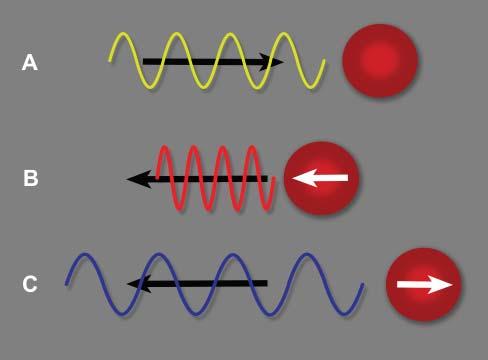

Dopplerultrasoundisbasedontheinteractionof ultrasoundwithparticlesinmovement,leadingto achangeinthefrequencyoftheechoesreceived, thisphenomenonisknownasthe Dopplereffect (Figure1.10)(Boote2003).Thiseffectisdisplayedand evaluatedwithcolorschemeswhenusingcoloror powerDopplermodes,orgraphicallywithspectral Doppler(Figures1.11,1.12).Thenumerousapplicationsofthesemodesarehighlightedinseveralfigures throughoutthebook,andparticularlyinChapter6.

Figure1.10. Dopplereffect.A: Theultrasoundpulseemittedbytheprobemovesindirectionofaredbloodcell(RBC) ataspecificfrequency. B: IftheRBCmovestowardthispulse, apositiveDopplershiftoccurs,increasingthefrequencyof thereturningecho.Thewavelengthisreduced. C: IftheRBC movesawayfromthispulse,thefrequencyofthereturning echoisreducedanditswavelengthisincreased.Thisnegative Dopplershiftisdisplayedasabluesignalinthestandardcolor Dopplermode,whereasbloodflowmovinginthedirectionof theprobeisdisplayedinaredhue.